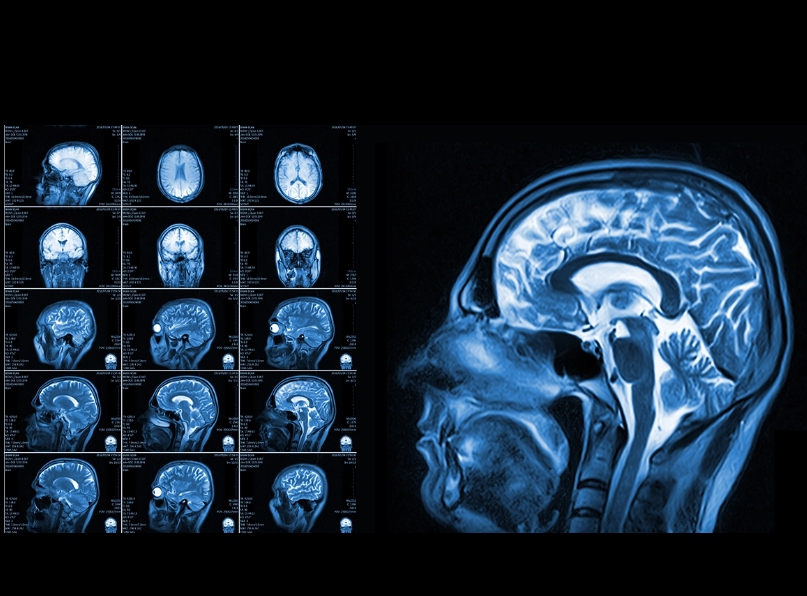

MRI는 검사 시간이 긴 편이에요. 부위마다 다르지만 보통 20분에서 길면 1시간 이상 걸리기도 해요. 가만히 누워 있어야 하고, 검사 중에는 움직이면 안 돼서 힘들어하는 분들도 많아요. 좁고 어두운 공간이 불편한 분들은 폐쇄공포증을 느끼기도 해요. 제 지인은 MRI 찍다가 너무 답답해서 중간에 멈춘 적도 있었어요. 요즘은 개방형 MRI도 있어서 그런 불편을 줄여주긴 합니다.

뇌 쪽 검사도 목적에 따라 달라요. 뇌출혈이나 외상이 의심되면 빠르게 판단 가능한 CT가 먼저 쓰입니다. 실제로 제 지인은 갑자기 두통과 어지러움이 심해져서 응급실에 갔는데, CT로 바로 뇌출혈 여부를 확인했어요. 이후 좀 더 정밀한 확인이 필요해 MRI도 찍었는데, 작은 병변까지는 MRI가 훨씬 잘 보여준다고 하더라고요. X-ray는 뇌 자체보다는 두개골 상태를 볼 때 사용돼요.

병원에 가면 MRI나 CT 찍자고 하는 경우가 종종 있어요. 겉보기엔 비슷해 보여도 이 둘은 검사 방식부터 목적까지 완전히 다릅니다. 제 친구는 얼마 전 무릎 통증으로 병원을 갔는데, 의사 선생님이 X-ray 먼저 찍고 나중에 MRI를 추가로 권하더라고요. 알고 보니 뼈 상태는 괜찮은데 인대 손상이 의심돼서 MRI로 확인해야 했대요. 이렇게 MRI는 자기장과 전파를 이용해 근육, 인대, 뇌처럼 부드러운 조직을 자세히 살펴볼 수 있고, CT는 X선을 여러 방향에서 쏴서 컴퓨터로 이미지를 만들어내기 때문에 응급상황에서 빠른 진단에 유리해요.